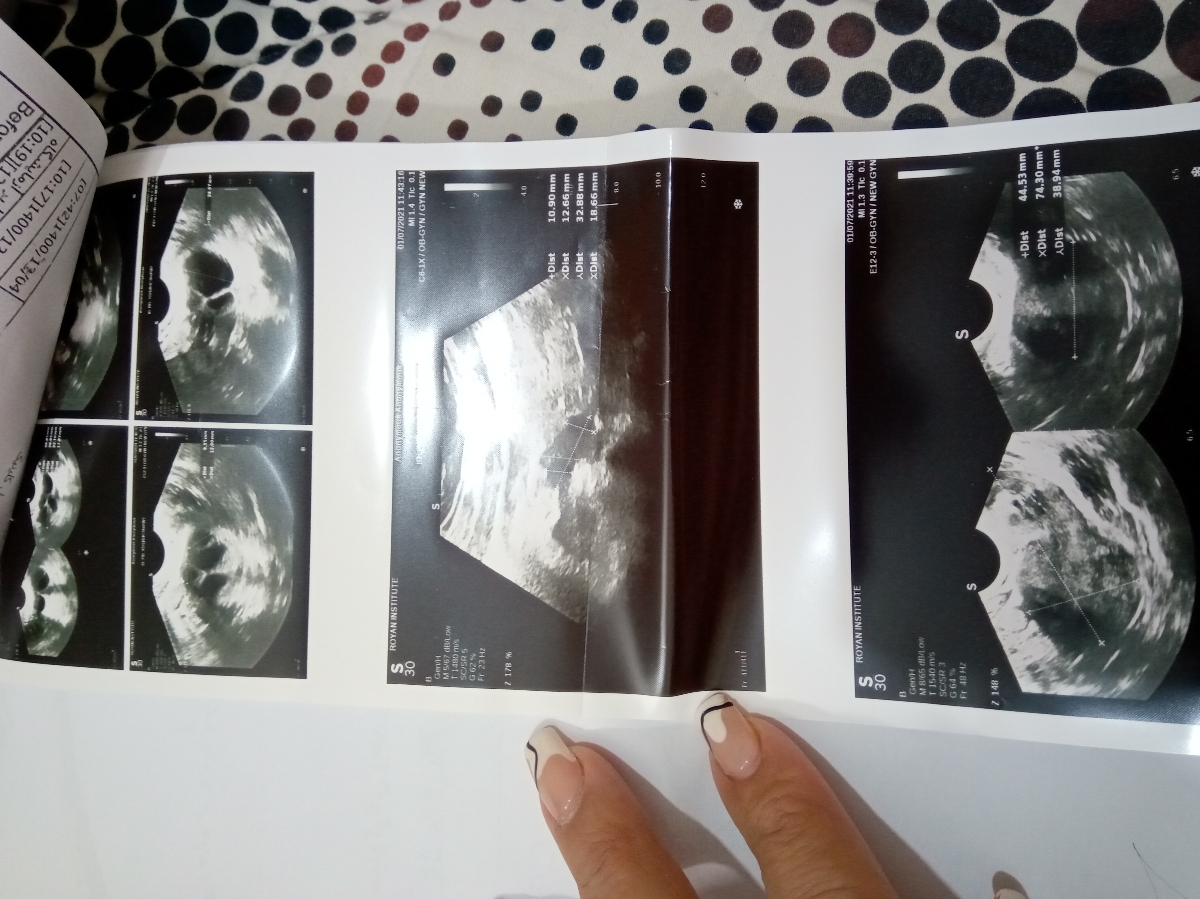

داروهای محرک تخمک گذاری چند نوبت انجام شده و عکس آزمایش همسرتان را ارسال کنید تا ببینم

اخری جواب عکس رنگی از لوله های رحم هست

آزمایش اسپرم همسرم و سونوگرافی بعدازمصرف داروهای تخمک گذاری